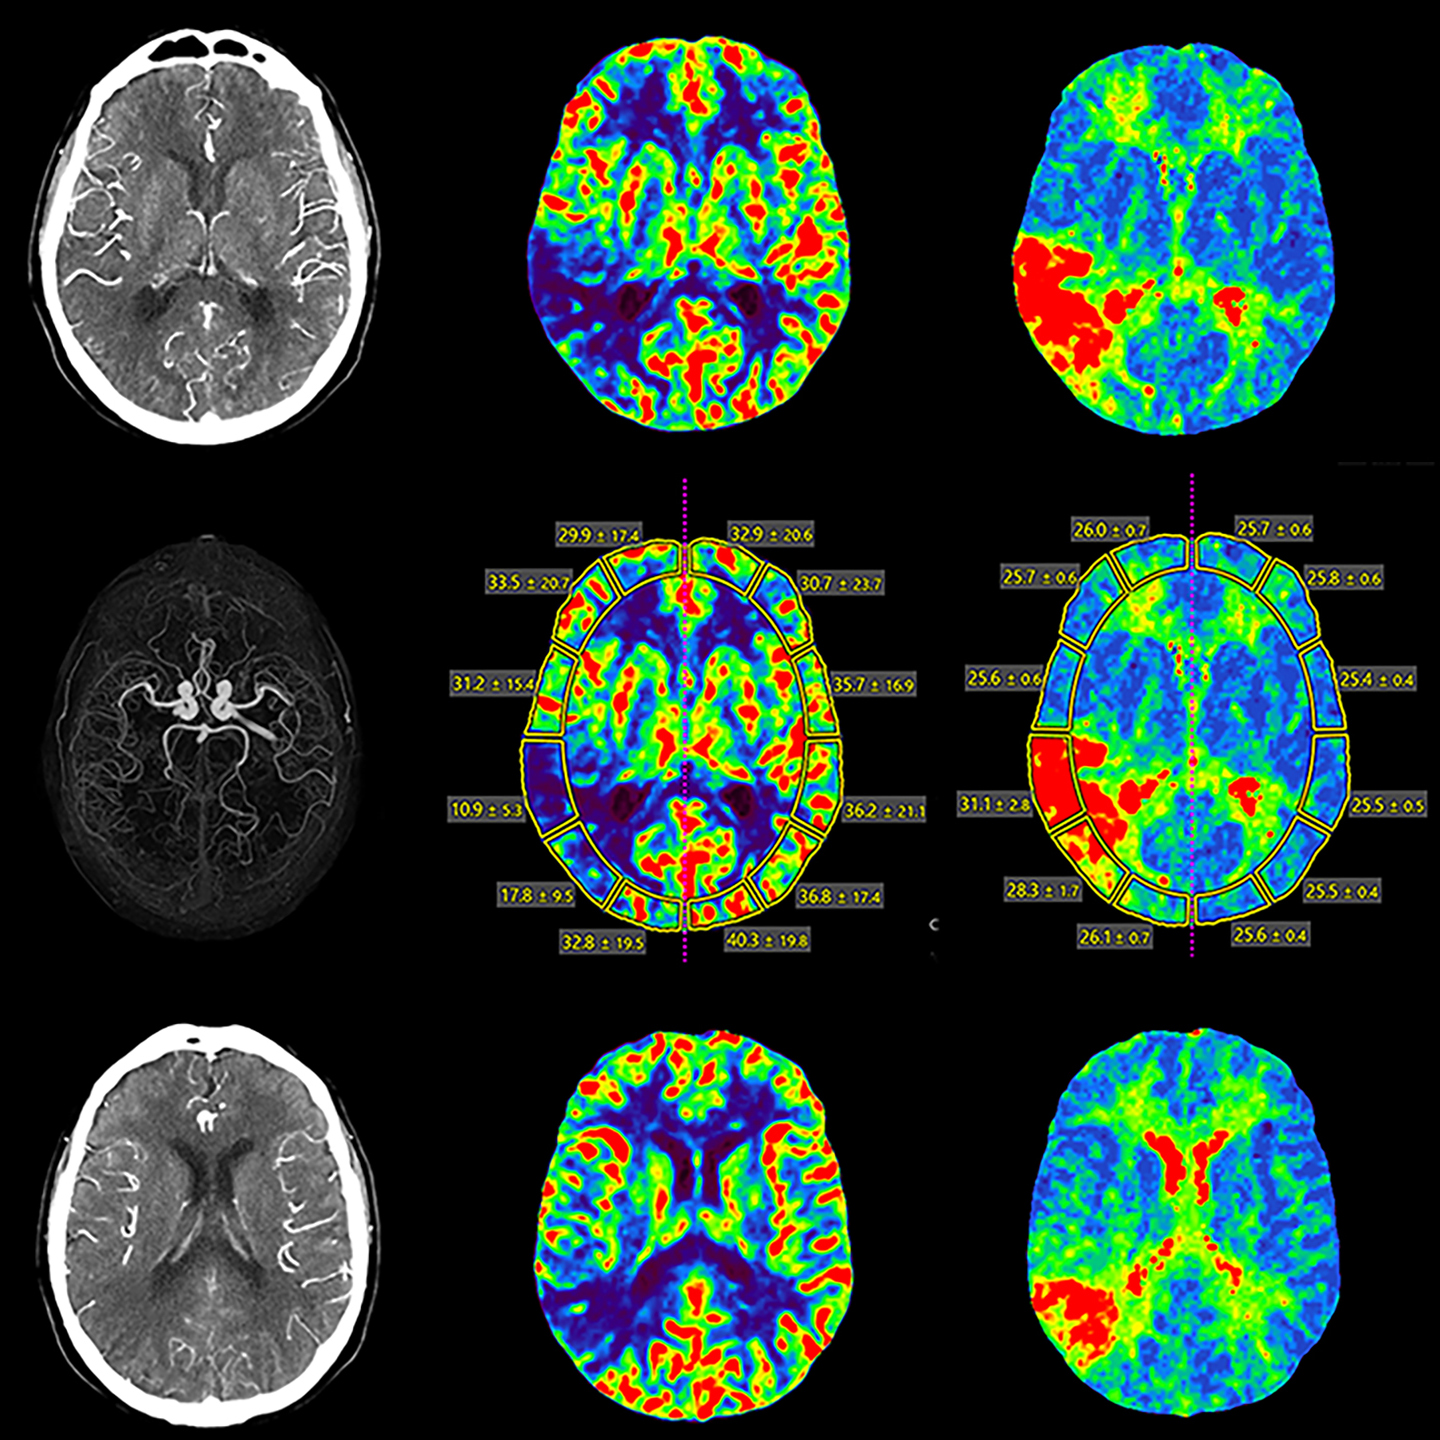

Спектральная визуализация с глубоким обучением

Система Deep Learning Spectral CT от Canon Medical была разработана, чтобы вывести ваши возможности визуализации на совершенно новый уровень.

Aquilion ONE (PRISM Edition) использует временные преимущества быстрого переключения кВ с модуляцией мА для конкретного пациента и сочетает их с реконструкцией глубокого обучения, которая обеспечивает превосходное разделение энергии и низкий уровень шума.